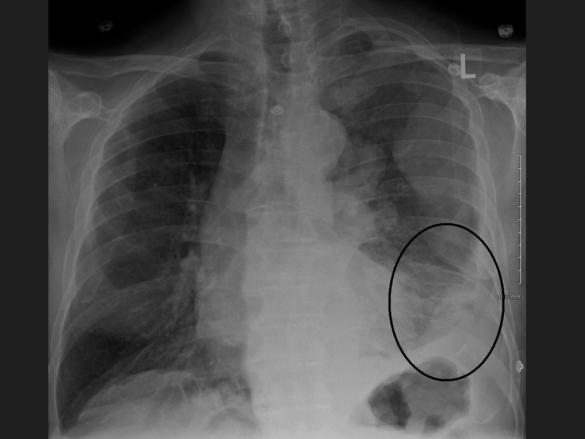

Imagem – Imagem de raio-X de tórax mostrando um mesotelioma pleural maligno (imagem: James Heilman, MD/Wikimedia Commons)

Causado pela exposição ao amianto (asbesto), o mesotelioma pleural maligno é um tipo de câncer raro, mas muito agressivo, com prognóstico de sobrevida de seis a 18 meses, o que torna necessária a identificação de novos marcadores preditivos e prognósticos para a doença.

Ela explica que a exposição às fibras do asbesto destrói as células mesoteliais normais da pleura, membrana que reveste o pulmão. A doença se desenvolve a partir do efeito combinado entre as células da pleura e os macrófagos (células de defesa) que fagocitam as fibras do asbesto.